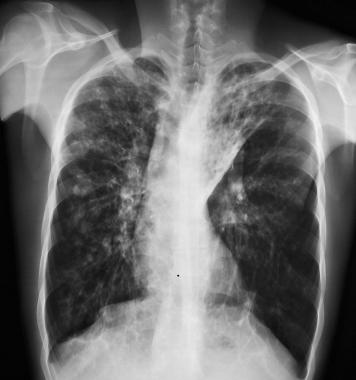

患有轻度肺部疾病的囊性纤维化患者的胸片可能正常。由于黏液堵塞而导致的肺部过度充气可能是儿童或成人时期的唯一表现。

中度或晚期时的肺部可能出现线状阴影和散在结节,并可能观察到节段性、斑片性或小叶性肺不张,儿童比成人更为多见,通常表现在右上叶。

图3 囊性纤维化患者双侧支气管扩张,并伴有左上叶肺不张

图4 右肺完全不张伴支气管扩张,注意左肺过度充气

图5 27岁患者仅有轻微症状,显示为支气管壁增厚、双侧小结节状浑浊和脊柱侧弯。